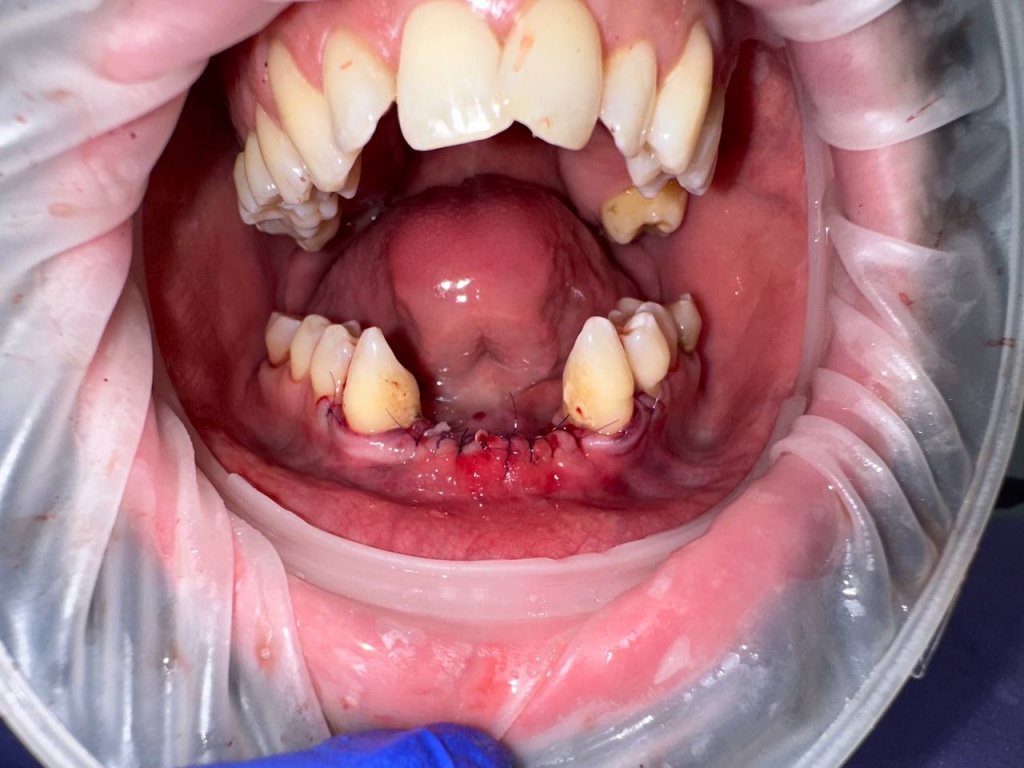

Уже много лет использую в своей практике имплантаты IMPRO. В этот раз мне предоставили линейку IMPRO Respect нового дизайна с широкими лепестками резьбы по отношению к телу имплантата. За счет чего получилось установить имплантаты в переднем отделе в узком гребне и с плохим костным предложением пациента. Ни разу не сталкивалась с осложнениями или проблем с имплантатми IMPRO Implantem. В этот раз не было исключением, была проведена операция через навигационный шаблон, имплантаты стабилизировались с хорошим торком. Хирургический набор и протоколы достаточно просты и удобны. Будем ждать ортопедической части, спустя месяц имплантаты стоят хорошо!

Пациент — мужчина 54 года.